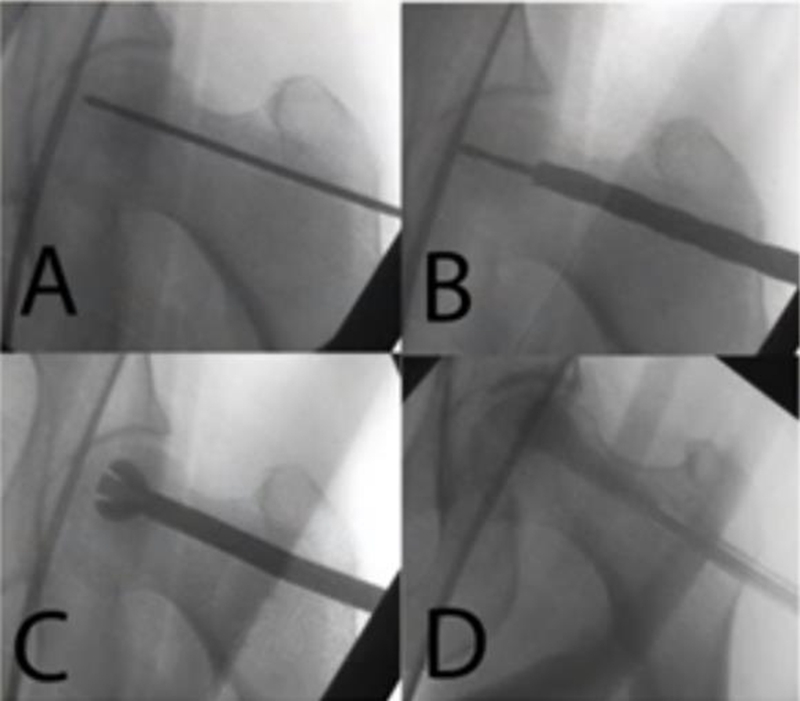

4、改良髓芯减压术(advanced CD,ACD)

由于CD术后缺乏有效的力学支撑,会增加股骨头塌陷和骨折的风险,因此,为了增强股骨头的机械强度,防止股骨头塌陷,CD联合支撑物治疗是目前临床上常用的治疗策略。

通过髓芯减压后联合骨移植(非血管化骨移植/血管化骨移植),以获得良好的支撑。支撑物包括自体骨、异体骨、人工骨、骨移植复合物等。

髓芯减压联合非血管化骨移植术最早由Phemister在1930年报道,骨移植给股骨头坏死区域提供了结构支撑或者起到支架作用促进骨重建。最常见的是通过髓芯减压通道植入,还有trap door technique 和light bulb procedure技术。

非血管化骨移植考虑到减少供区的发病率以及较少的技术要求更受临床欢迎。目前,供区分离骨移植模式很少单独使用,一项长达14年的随访研究发现,非血管化骨移植治疗临床效果较差。需要技术改进结合生长因子或者骨移植替代物进行骨重建。国内学者应用髓芯减压联合打压植骨术治疗ARCO Ⅱ、Ⅲ型股骨头坏死,平均随访24个月,结果股骨头存活率达81%,平均HSS评分由术前61增加到86。